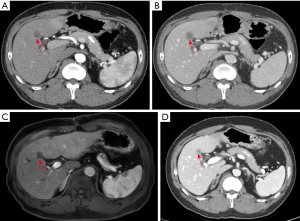

The third patient was a 55-year-old male who had been diagnosed with rectal adenocarcinoma and bilateral renal cell carcinoma 2 years ago. Preoperative abdominal CT examination revealed an ill-defined, low attenuating lesion in segment S5 of the liver (measuring <1 cm). The laboratory examinations showed no obvious evidence of infection signs such as increased CRP level or WBC counting. Therefore, the initial diagnosis was focal fat deposition, and metastasis is less likely. Since the lesion was very small, no interventional treatments were administered, and a close follow-up was suggested. He underwent rectectomy and bilateral nephrectomy and sustained on long-term hemodialysis after the operation. However, the follow-up CT and MRI examinations in the half a year after the surgery revealed that the previous nodule in segment S5 of the liver increased in size from 1 to 2 cm with peripheral enhancement after administration of contrast agent (Figure 3). The F-18 FDG PET-CT demonstrated a hypermetabolic nodule in S5 of the liver, which indicated a high suspicion of hepatic metastasis. Finally, the successful FNA was done on this nodule of the liver. Microscopically, the nodule exhibited a caseating granuloma with a mixture of epithelioid histiocytes, inflammatory cells and Langhans giant cells in the background of fibrous tissue (Figure 4). Moreover, further NTM and MTB PCR kit revealed positive for NTM and negative for MTB. The patient received antitubercular treatment and was responsive to therapy. The latest follow-up CT showed the nodule decreased slightly from 2 to 1.4 cm in size and no other newly appeared lesions in the liver (Figure 3D).